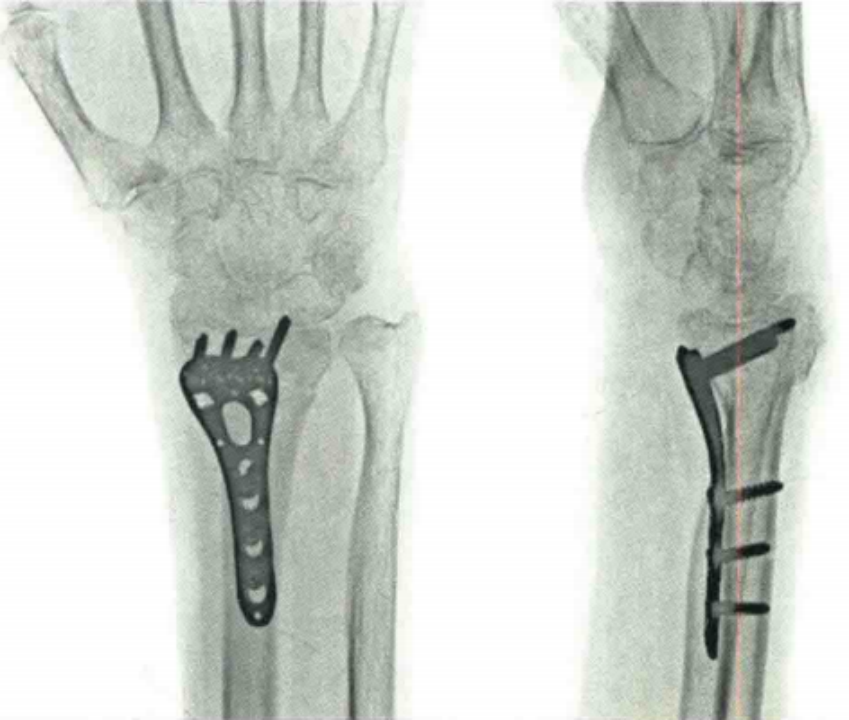

小结

医疗康复包括什么骨质疏松性骨折:诊断、治疗和康复一文整理!_https://www.jmylbn.com_新闻资讯_第2张

总之,对于骨质疏松骨折,除了治疗骨折、功能锻炼外,抗骨质疏松治疗一定要贯穿整个骨质疏松骨折的全过程。